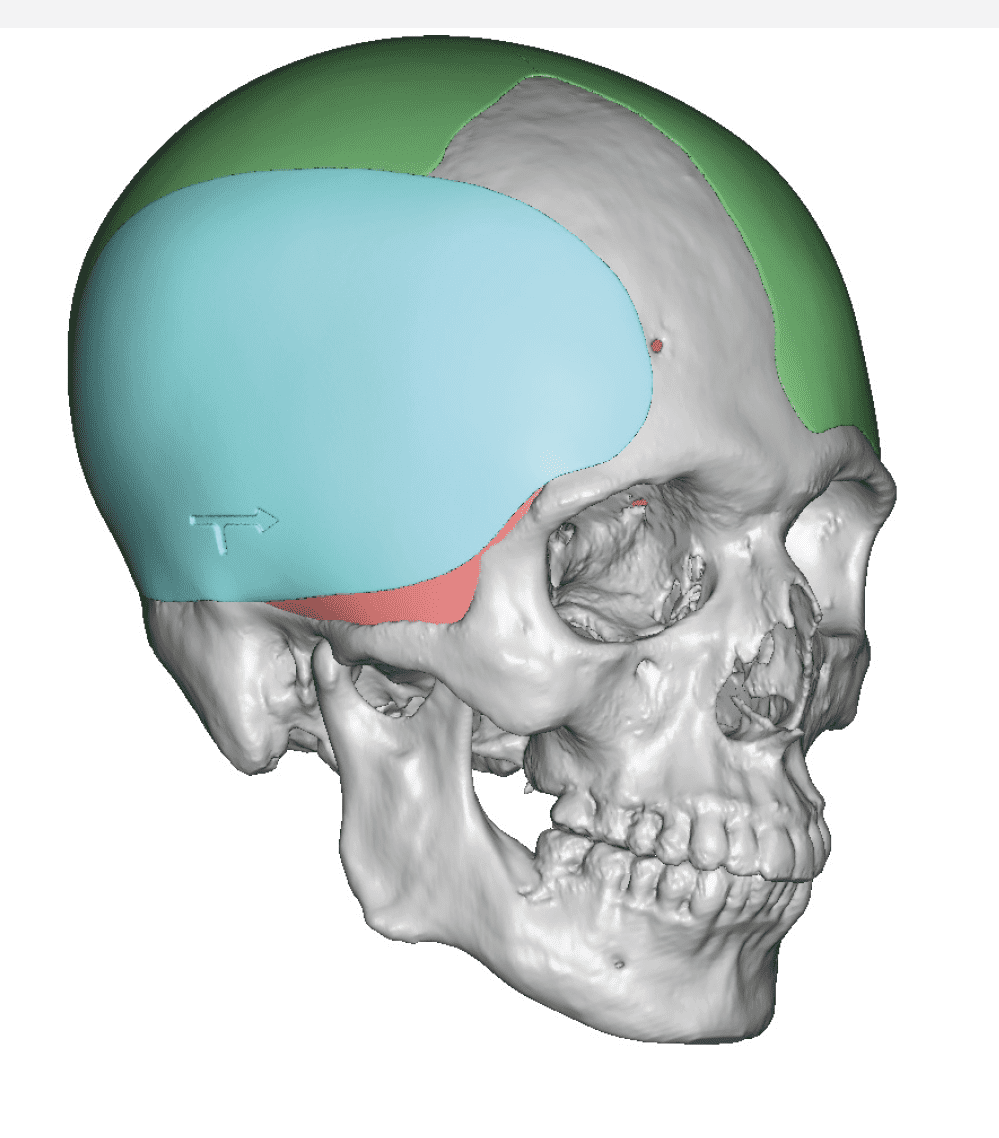

Desire for change of head shape from front view form an inverted V shape to a rounder and wider head shape.

Placement of custom extended forehead-temporal implants through incisions in the crease behind the ear. (he had a prior back of head skull implant which is green in the implant designs and which the head widening implants partially covered it)

Desire for change of head shape from front view form an inverted V shape to a rounder and wider head shape.

Placement of custom extended forehead-temporal implants through incisions in the crease behind the ear. (he had a prior back of head skull implant which is green in the implant designs and which the head widening implants partially covered it)